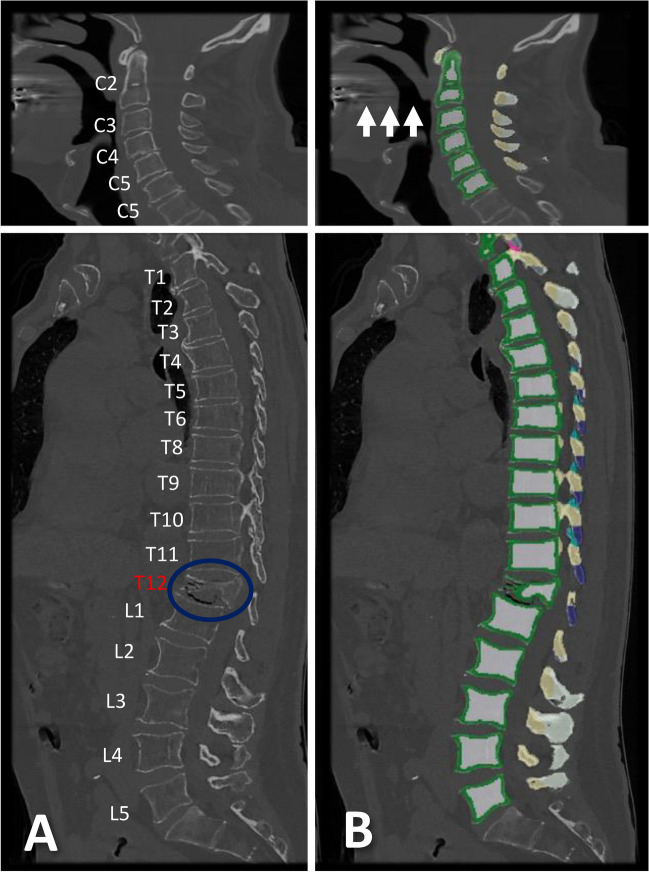

Methods: Three hundred twenty-five patients (65.3 ± 19.2 years, 140 women) with routine non-contrast or contrast-enhanced multi-detector CT (MDCT) scans were included. Trabecular vBMD was automatically extracted from each vertebra using a convolutional neural network (CNN)-based framework (SpineQ software v1.0) with asynchronous calibration and contrast phase correction. The correlations of vBMD between each vertebra spanning C2-T12 and the averaged lumbar spine (L1-L3, or L4 and L5) vBMD values were analyzed, considering fracture status and degeneration. Vertebra-specific linear regression equations were used to approximate lumbar vBMD at the cervicothoracic spine.

Results: Cervicothoracic vBMD correlated well with lumbar vBMD (r = 0.79), with significant improvement after excluding degenerated vertebrae (p < 0.05; r = 0.89), except for C7-T3 and T9. Cervical (AUC = 0.94) and thoracic vBMD (AUC = 0.97) showed strong discriminatory ability for osteoporosis (vBMD < 80 mg/cm3). Excluding degenerated vertebrae at the cervical spine increased the AUC to 0.97. Cervical and thoracic vBMD (AUC = 0.74, AUC = 0.72) were comparable to lumbar vBMD (AUC = 0.72) in differentiating patients with and without prevalent VFs. Trabecular vBMD < 190 mg/cm3 for the cervical spine and < 100 mg/cm3 for the thoracic spine were potential indicators of osteoporosis, similar to < 80 mg/cm3 at the lumbar spine.